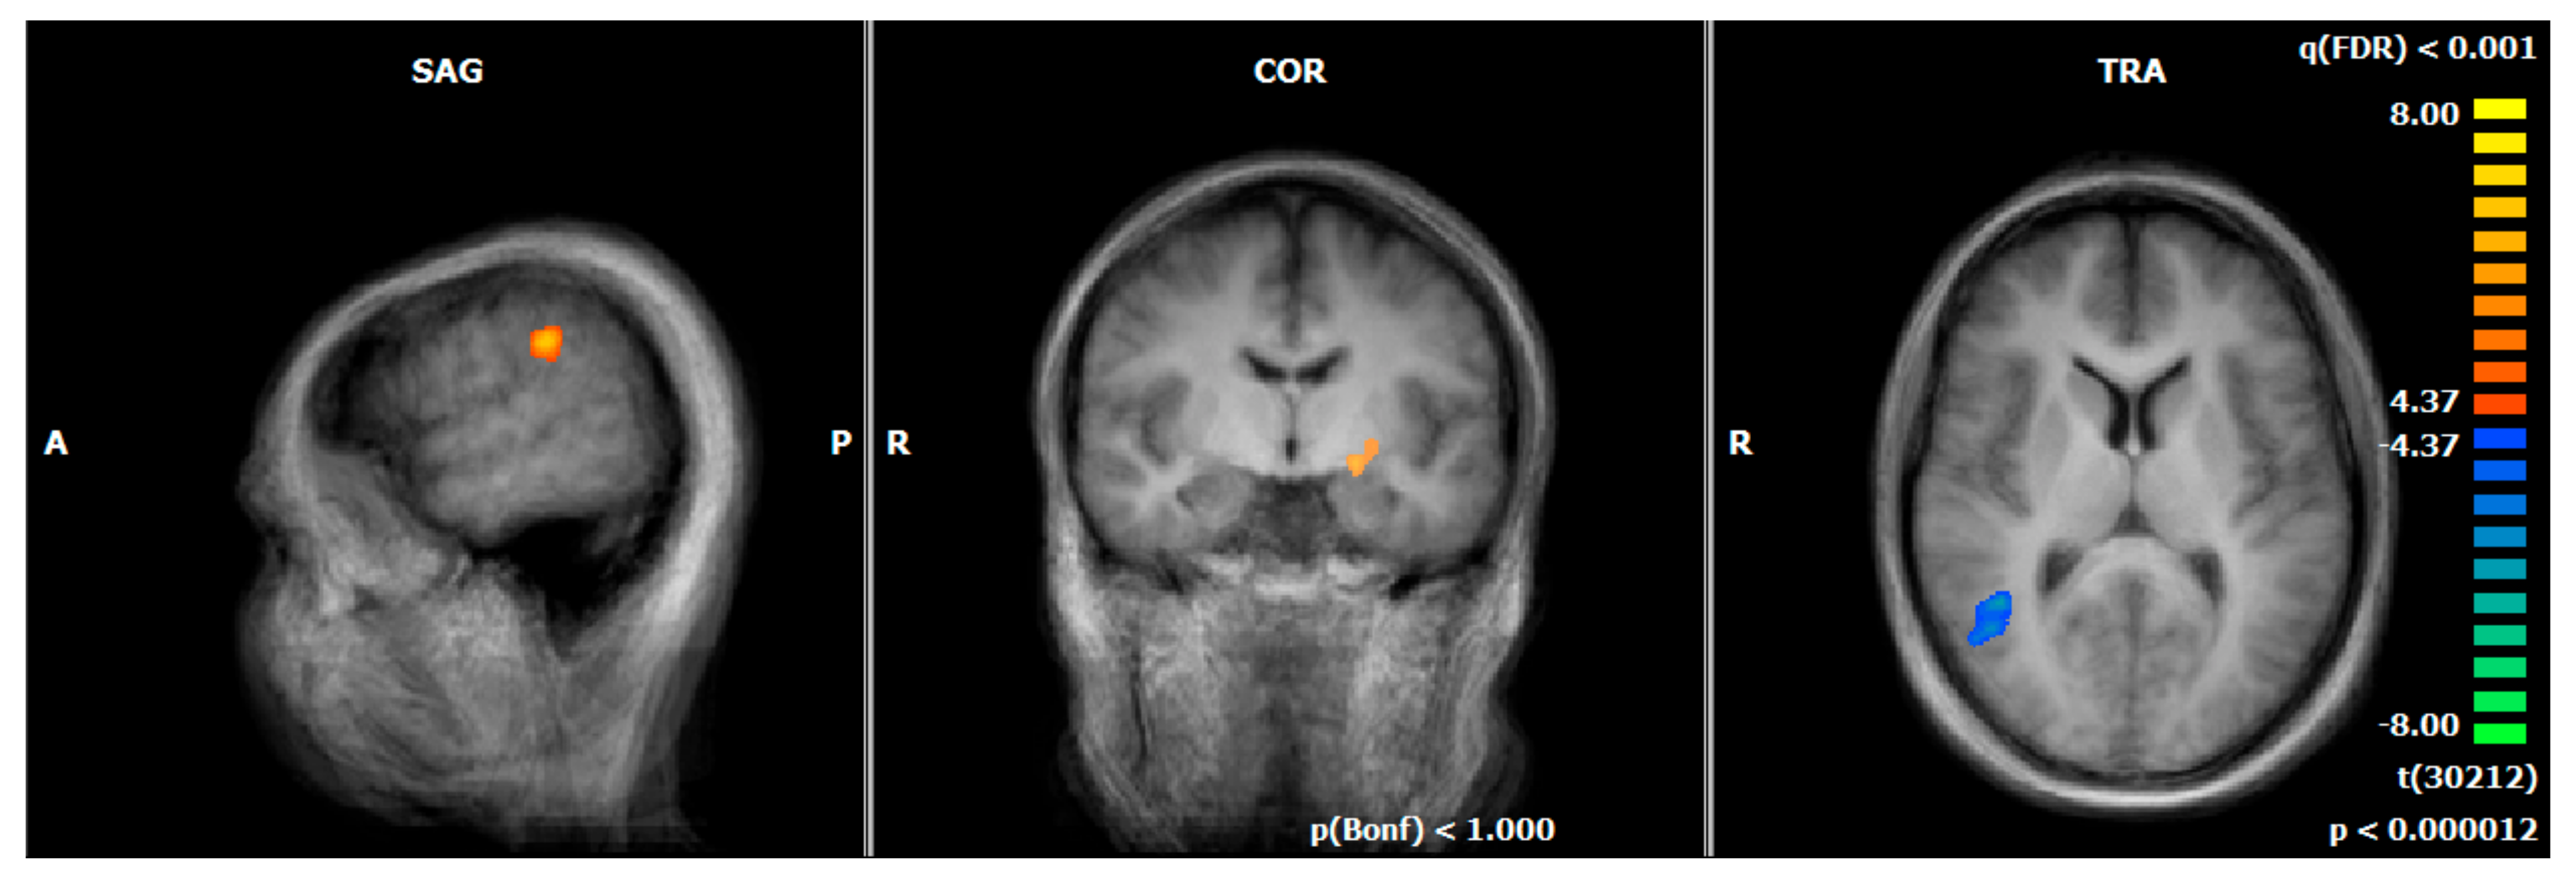

3.6. Comparison of Hemodynamic Responses between the MDD REAL and HC REAL: First vs. Last NF Run

4.2.4. Comparison of Hemodynamic Responses between the MDD REAL and HC REAL: First vs. Last NF Run